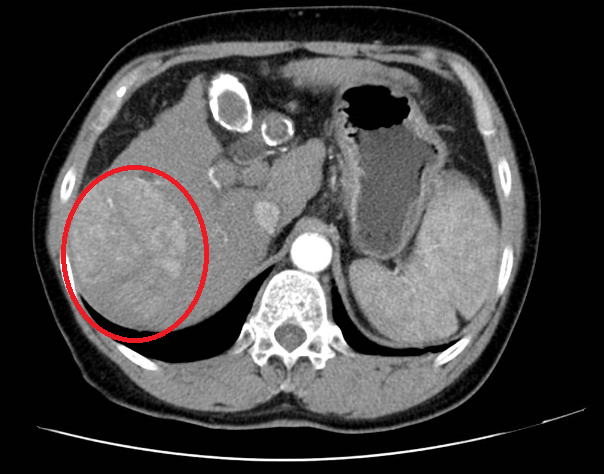

上腹部增強(qiáng)CT

診斷原發(fā)性肝癌明確,并丙型肝炎病毒復(fù)發(fā)。